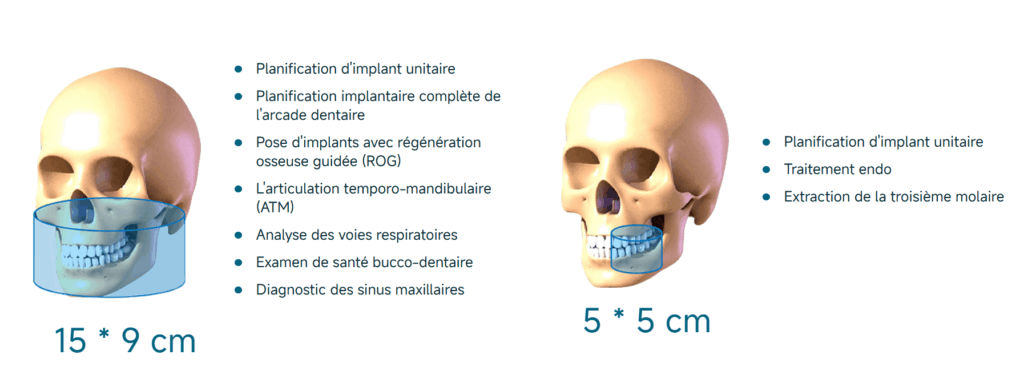

2 CHAMPS DE VISION